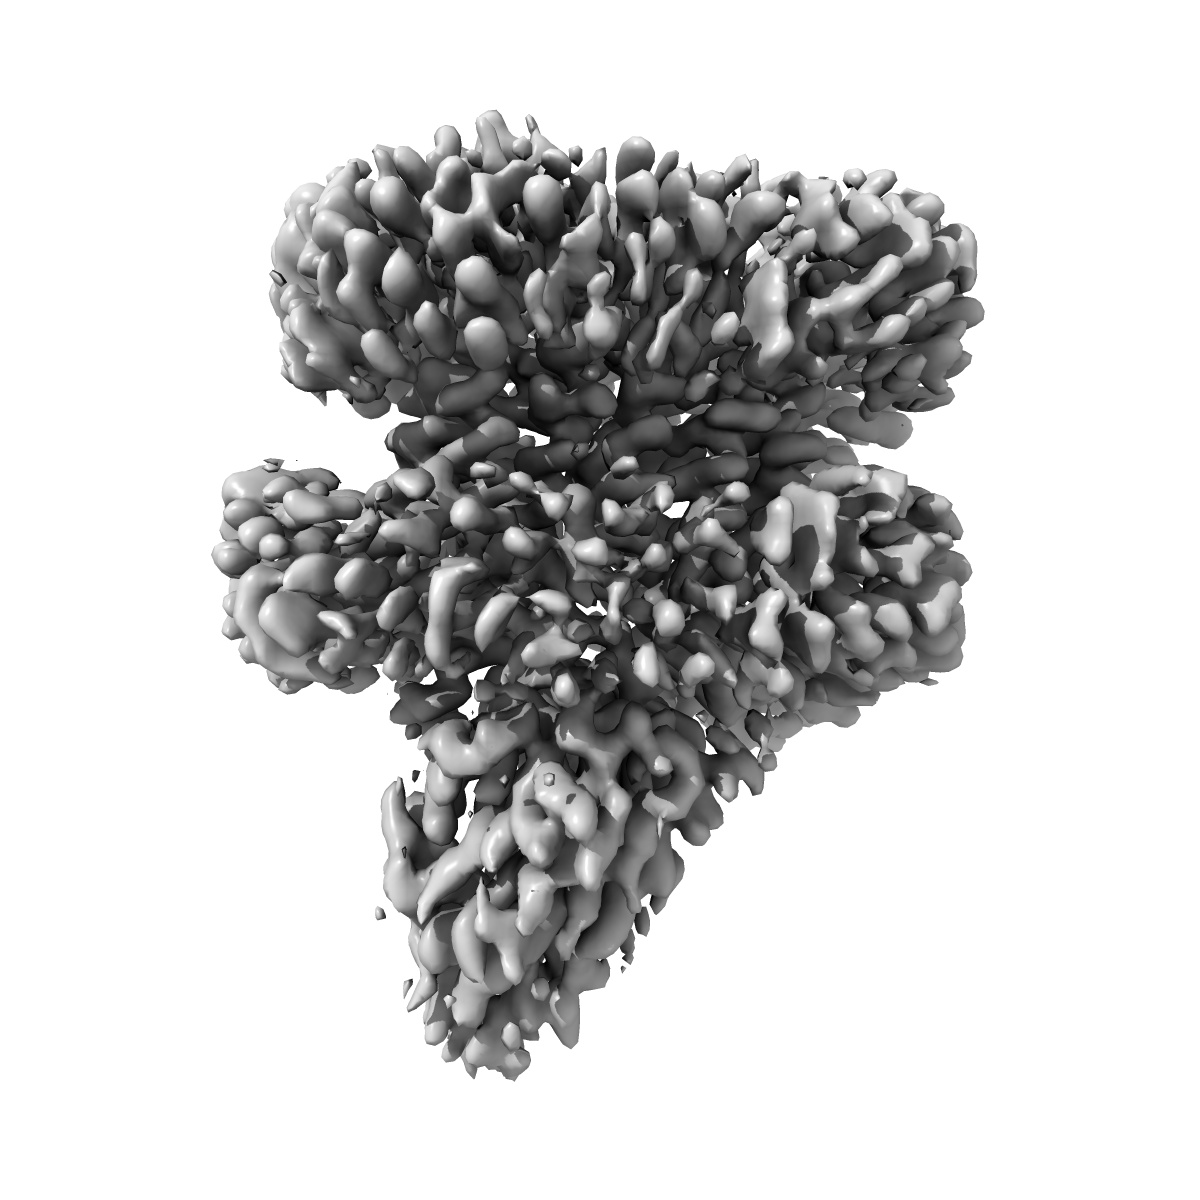

Cryo-EM structure of the proton coupled folate transporter at pH 6.0 bound to pemetrexed

Single-particle3.3 Å

Sample: Complex of the proton coupled folate transporter at pH 6.0 bound to pemetrexed

Structural basis of antifolate recognition and transport by PCFT.

(2021) Nature , 595 , 130 - 134